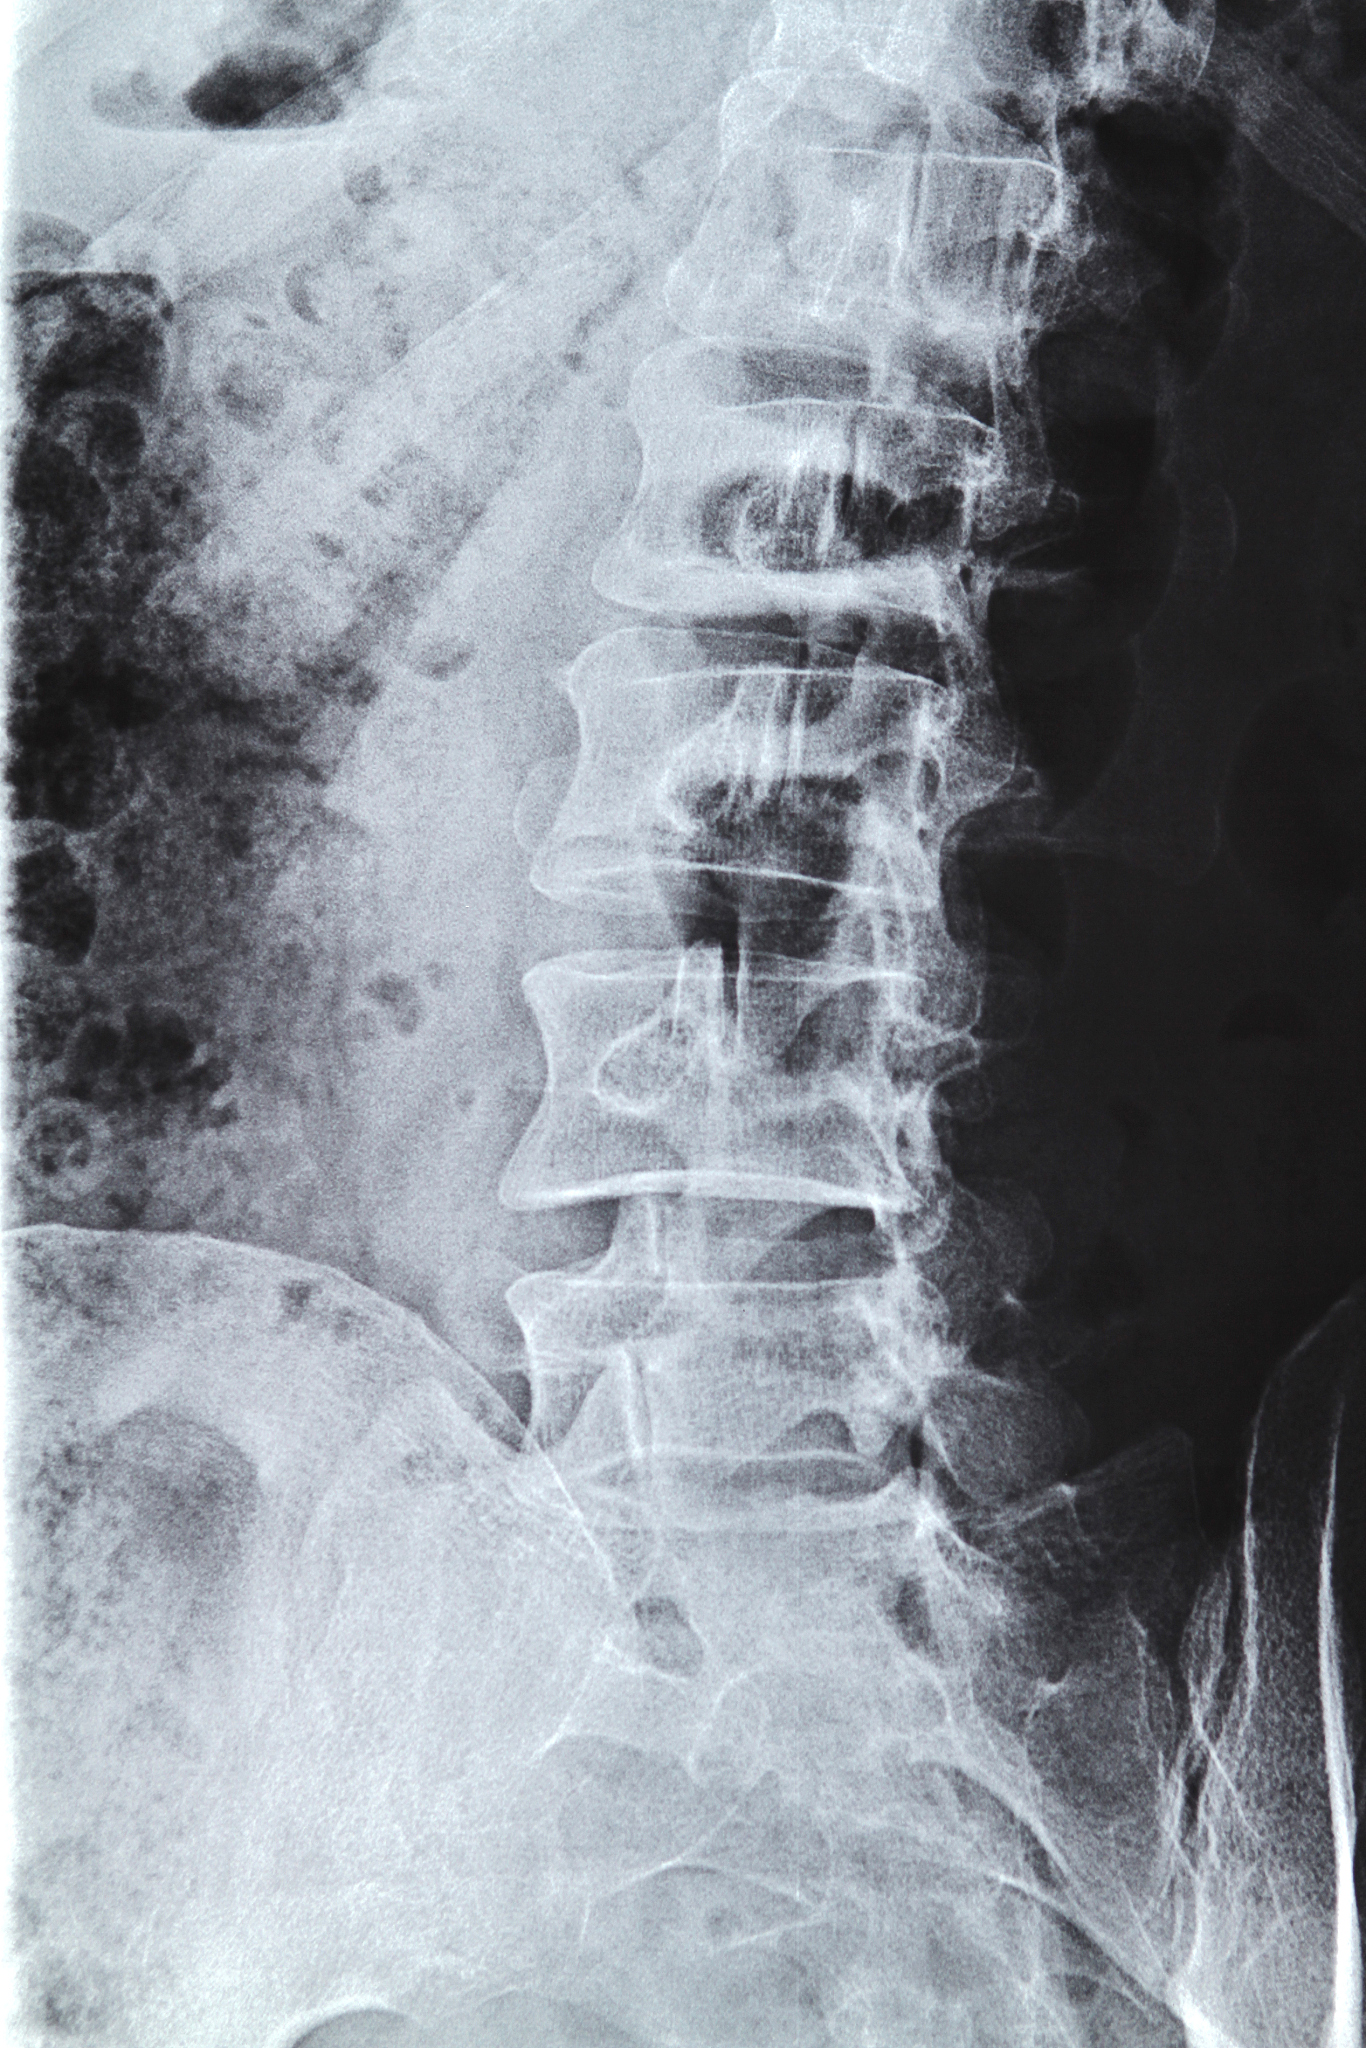

椎体成形术(PVP)是一种治疗椎体骨折和骨质疏松所引起的背部疼痛的手术方法。该手术的主要功能治疗如下:

1. 疼痛缓解:PVP手术通过将特殊的骨水泥注入到椎体骨折的空洞中,稳定骨折的椎体,减少疼痛症状。骨水泥填充了椎体的空腔,增加了椎体的稳定性,减少了骨折处的移动和疼痛。

2. 恢复功能:椎体骨折可能导致椎体的塌陷和变形,进而影响脊柱的正常功能。通过PVP手术,填充骨水泥可以恢复椎体的高度和形态,恢复脊柱的正常功能。

3. 增加稳定性:椎体骨折和骨质疏松可能导致脊柱的不稳定性。PVP手术通过填充骨水泥加固椎体,增加了椎体的稳定性,减少了骨折处的移动,从而减轻了背部疼痛和预防了进一步的骨折。